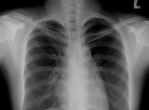

最近身边的朋友都在讨论一个话题,那就是做CT到底伤不伤身体。这让我想起了自己第一次做CT的经历,心里不禁泛起了涟漪。那么,今天我们就来聊聊这个话题,看看做CT到底有没有那么可怕。CT扫描,你了解多少?首先,让我们来了解一下什么是CT扫描。CT,全称是计算机断层扫描,是一种医学影像技术。它通过X射线从多个角度照射人体,然后通过计算机处理这些数据,生成人体内部的断层图像。听起来是不是很神奇?没错,CT扫描在医学诊断中扮演着非常重要的角色。CT扫描,安全吗?那么,做CT扫描到底伤不伤身体呢?这个问题让...